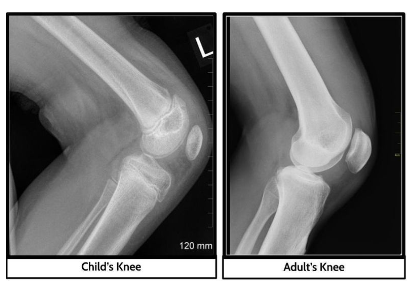

Part 1: What happens at the growth plate within bones as a child grows into an adult?

We made observations of x-rays from children and adults and found out that there are gaps called growth plates in between different bones in children. The image to the right is an xray of a knee of a child and an adult.

On this assessment, you will apply what you have figured out about how our body heals to fill gaps from injuries to explain what happens to the structures of the bone at the growth plate as a child grows into an adult. On the image below, circle one part of the body where there is a growth plate that you will focus on in your explanation.